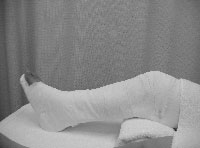

患部の固定、腫脹軽減を目的に脛骨内果部の後方、側方より圧迫枕子を加えた。腓骨は転位がないため前後方向からの圧迫枕子のみとした。両骨とも患部の動揺を防ぐため、テープによる固定を行った。冷湿布を行い、大腿中央より足先にかけて背側にクラーメルシーネをあて、包帯にて固定を行った。固定肢位は膝関節軽度屈曲位、足関節良肢位とした(図3)。右患側肢への体重付加を禁止。松葉杖歩行を指示した。

クラーメル、包帯による固定 |